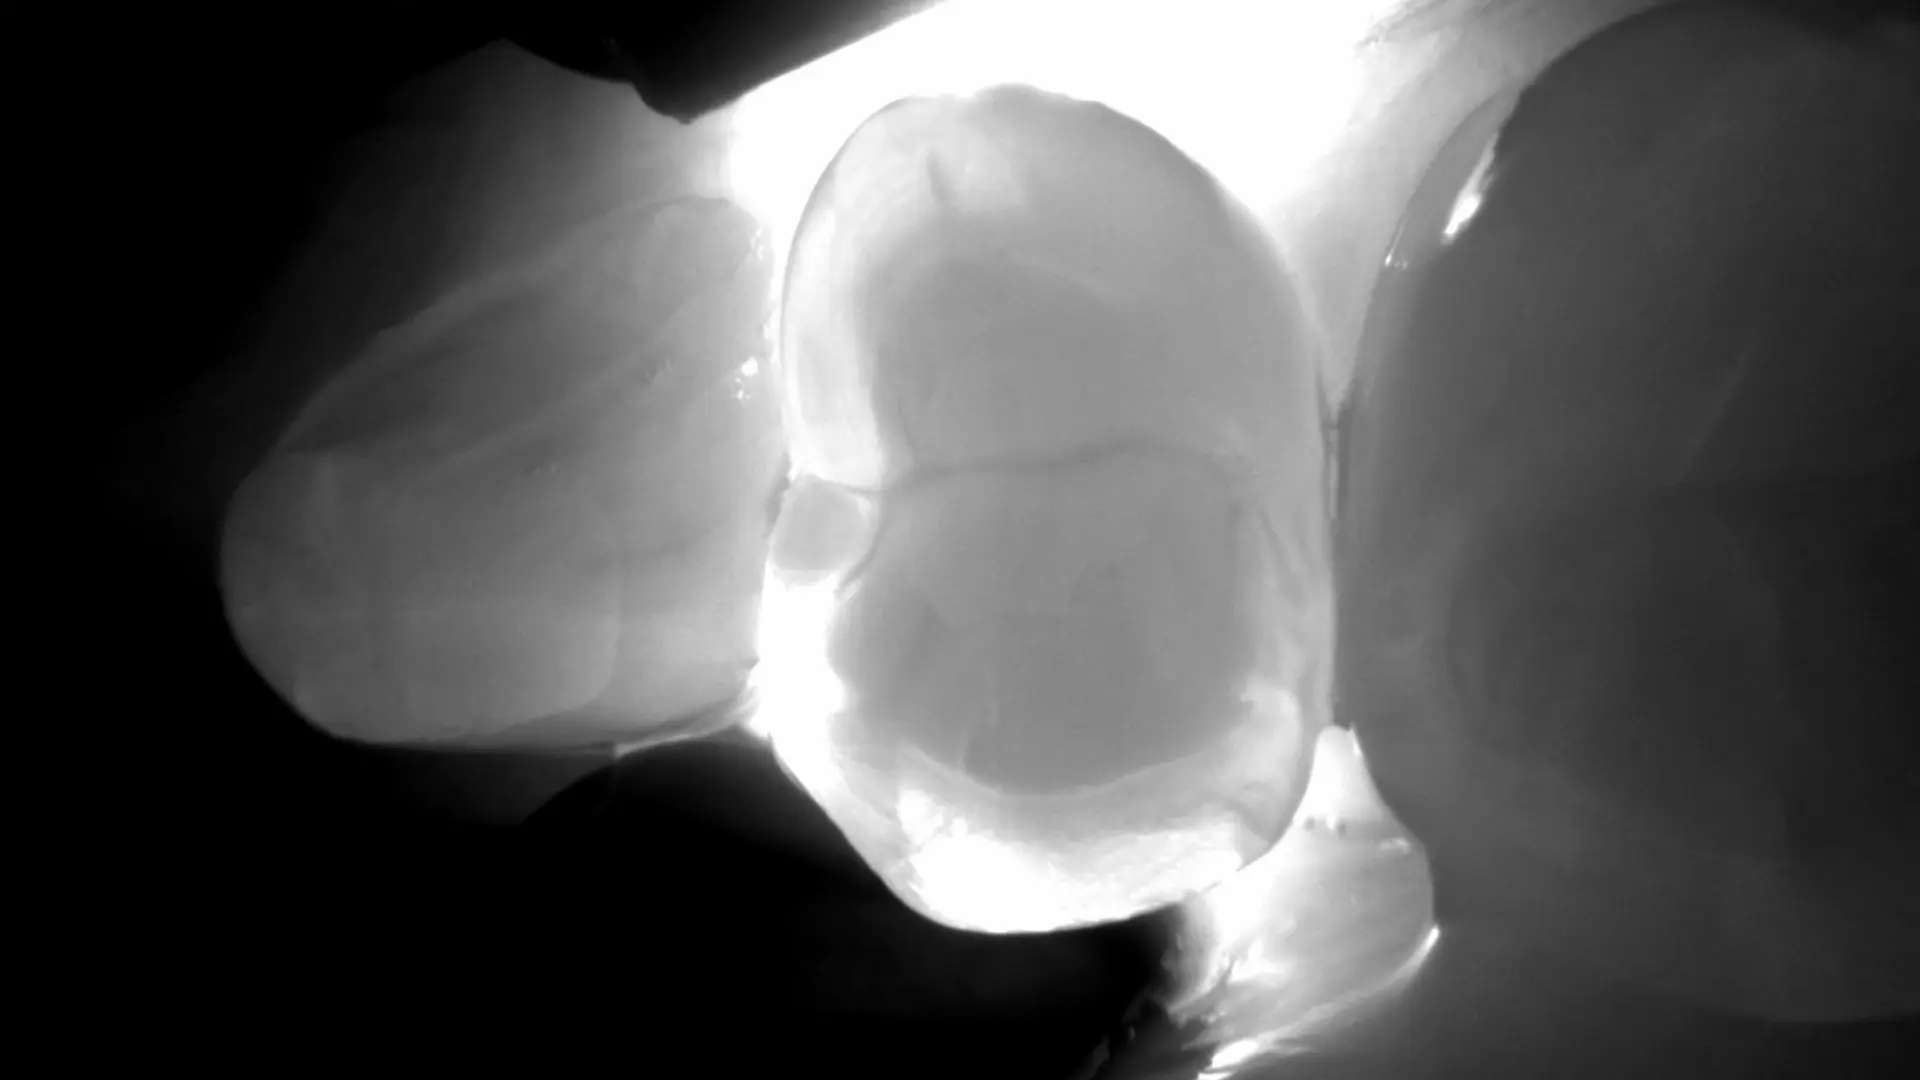

Die DIAGNOcam nutzt ein einfaches, aber geniales Prinzip: Licht statt Röntgenstrahlung. Dabei wird der Zahn mit einem speziellen Licht durchleuchtet (Transillumination). Gesunde Zahnsubstanz leitet das Licht weiter – kariöse Bereiche dagegen erscheinen dunkler. So können wir auch versteckte Karies in den Zahnzwischenräumen frühzeitig erkennen – ganz ohne Röntgenbild.

Die DIAGNOcam macht unsichtbare Stellen sichtbar. Insbesondere Karies im Zahnzwischenraum erkennt man oft nicht mit dem bloßen Auge. Und wenn man darauf wartet, dass es wehtut, ist es meist schon zu spät. Mit der Lichtdiagnostik prüfen wir ganz einfach, ob Handlungsbedarf besteht – sicher, schnell und sanft.